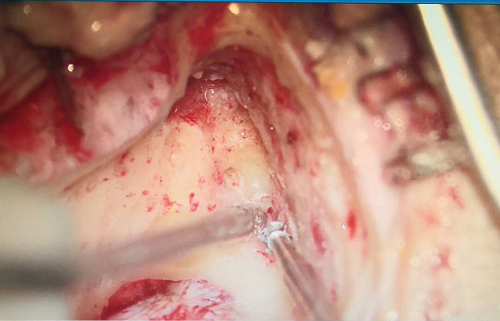

425日,我院耳鼻喉科胡少爭主任聯(lián)合河南省人民醫(yī)院劉軍教授為患者實(shí)施登封首例“乳突根治術(shù)+內(nèi)淋巴囊減壓術(shù)+半規(guī)管填塞術(shù)”該手術(shù)全程在顯微鏡下進(jìn)行,操作精細(xì)。術(shù)后患者無發(fā)熱、感染、面癱等手術(shù)并發(fā)癥出現(xiàn),恢復(fù)效果滿意。